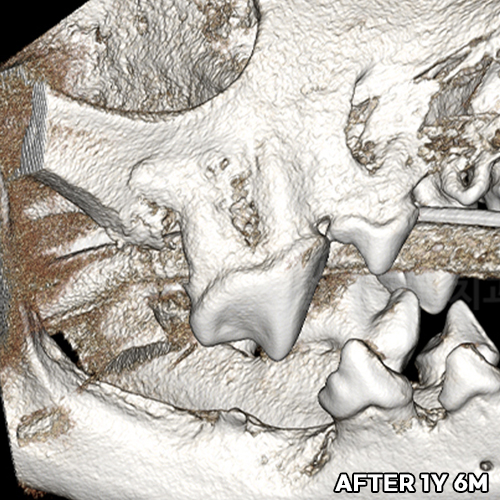

[강아지 잇몸에 고름] 최소침습적 발치 후 씨티로 확인된 자기잇몸뼈 증식! 치조골 살리는 힐링힐스 동물치과병원

2025.10.27